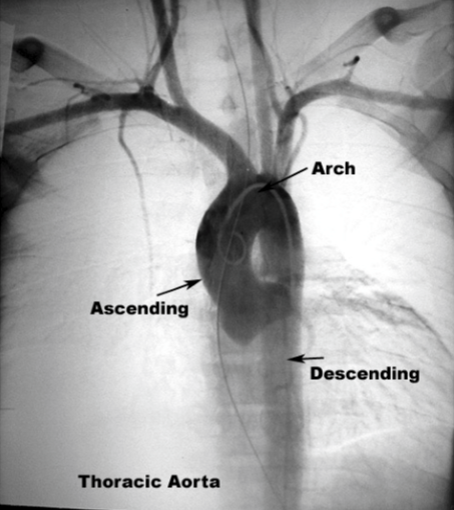

Label